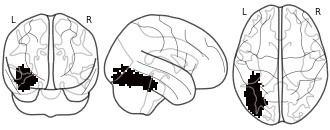

rois: trimmed ffa left

- neurovault.org

EmailClick to copy linkLink copied Cite(2016). rois: trimmed ffa left [Dataset]. http://identifiers.org/neurovault.image:15691niftiAvailable download formatsUnique identifierhttps://identifiers.org/neurovault.image:15691Dataset updatedFeb 1, 2016License

Cite(2016). rois: trimmed ffa left [Dataset]. http://identifiers.org/neurovault.image:15691niftiAvailable download formatsUnique identifierhttps://identifiers.org/neurovault.image:15691Dataset updatedFeb 1, 2016LicenseCC0 1.0 Universal Public Domain Dedicationhttps://creativecommons.org/publicdomain/zero/1.0/

License information was derived automaticallyDescription - O